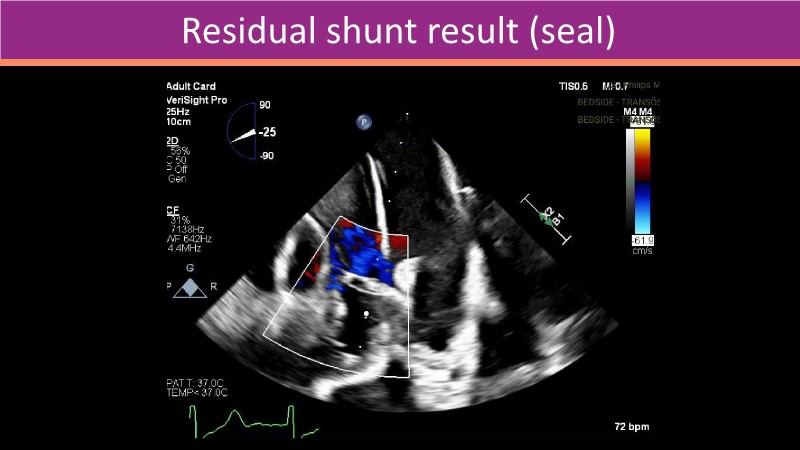

This PCR London Valves 2025 session explores how 3D TEE, 3D intracardiac echocardiography (ICE), and DeviceGuide technology sharpen procedural accuracy, strengthen operator confidence, and streamline decision-making in real time.

The session also includes detailed case analyses—such as Mitral TEER and LAA closure—and dual perspectives from both proceduralists and imagers.